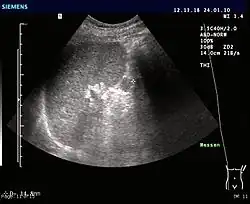

Śledziony dodatkowe (ang. accessory spleen) – nieprawidłowość anatomiczna polegająca na obecności jednej lub więcej dodatkowych śledzion. Są one w zasadzie wariantem normy, jako że są bardzo częste i z reguły bezobjawowe. W badaniach autopsyjnych stwierdzano do czterdziestu śledzion dodatkowych u jednej osoby. Lokalizacja śledzion dodatkowych zwykle jest lewostronna, w pobliżu wnęki śledziony, ale także wzdłuż tętnicy śledzionowej, trzustki, w więzadłach śledzionowych, torbie sieciowej, a nawet w mosznie (połączenie śledzionowo-mosznowe), płucach i sercu. Wielkość śledzion dodatkowych wynosi od 1 do 10 cm. Śledziony dodatkowe są często wykrywane przypadkowo przy okazji badań obrazowych: TK, USG, MRI, scyntygrafii. Istotne jest ich odnalezienie podczas wykonywanej z powodu hipersplenizmu splenektomii. Dodatkowa śledziona może ulec zropieniu, może wystąpić krwotok do dodatkowej śledziony lub torbiel.